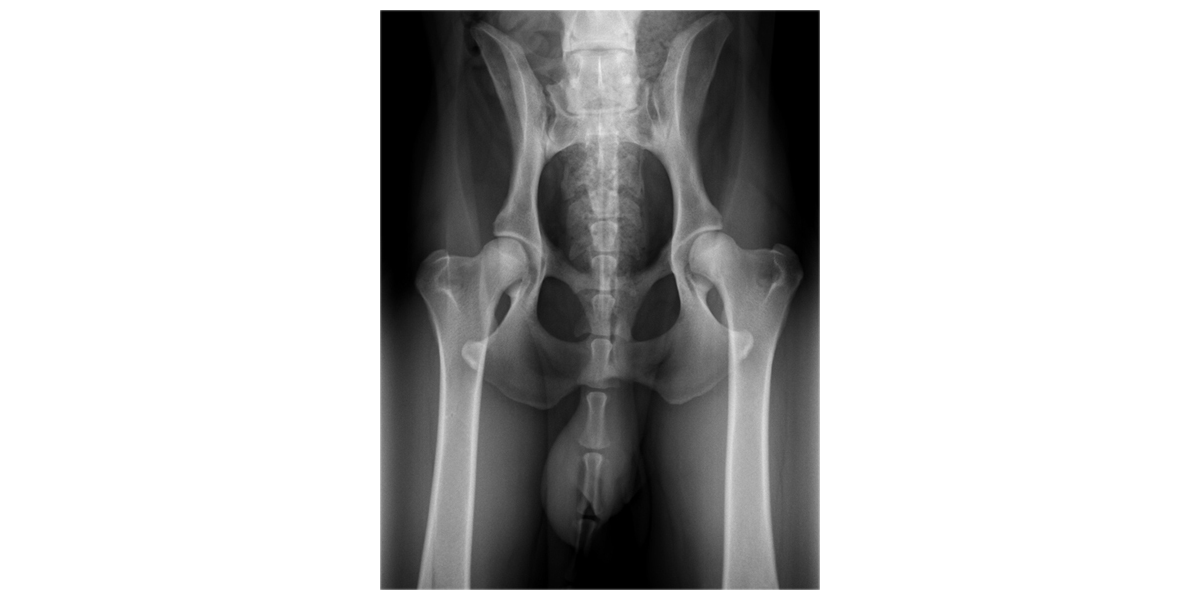

16 june 2013 * 71cm * 32kg * Pedigree * HD * Race Results

Click here for some good (in my eyes) information about Canine Hip Dysplasia